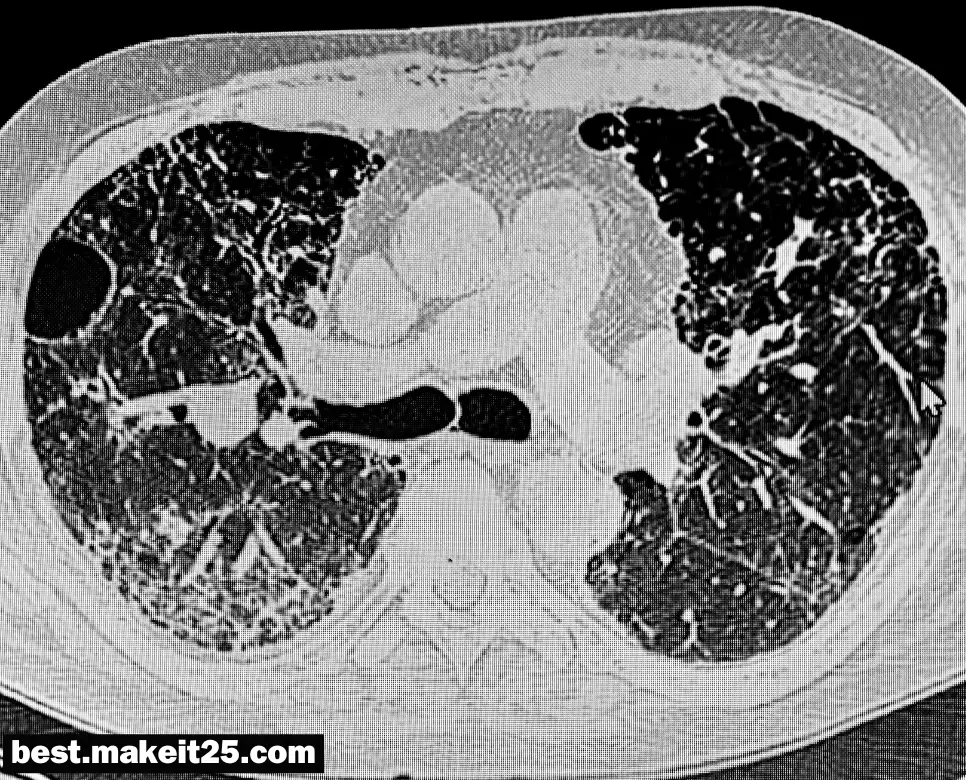

- 영상의학: X-레이, CT, MRI 등의 영상에서 RLL의 이상 여부를 확인할 때 사용됩니다.

RLL의 상태는 다음과 같은 영상학적 방법으로 평가될 수 있습니다:

- X-레이: 폐의 기본적인 구조와 이상 유무를 확인할 수 있습니다.

- CT 스캔: 더 상세한 이미지를 제공하여 작은 병변이나 이상을 확인할 수 있습니다.

- MRI: 조직의 상세한 이미지를 제공하여 병변의 성질을 평가할 수 있습니다.

RLL은 폐의 중요한 부위로, 호흡기 질환의 진단과 치료에 있어 핵심적인 역할을 합니다. 의료 전문가들은 RLL의 상태를 평가하여 환자의 건강 상태를 파악하고 적절한 치료를 제공합니다.